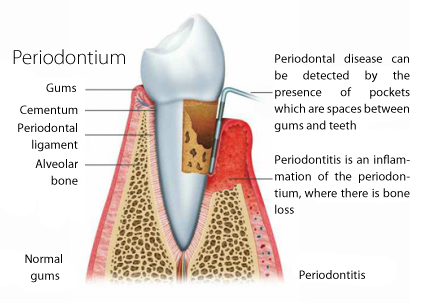

Periodontics is a medical term that, in dentistry, is about preventing, diagnosing and treating the diseases of the periodontium, which includes the gingiva (gums), alveolar bone, cementum, and the periodontal ligament.

The tissues that build the periodontium can suffer from injuries and they can have serious consequences if not treated in time.

In fact, periodontal disease is a bacterial infection of the periodontium. Microbes in the dental plaque can attack the gums, bone, and can cause the loss of the affected tooth.

Periodontal disease needs more time to develop, and the negative effects are not negligible.